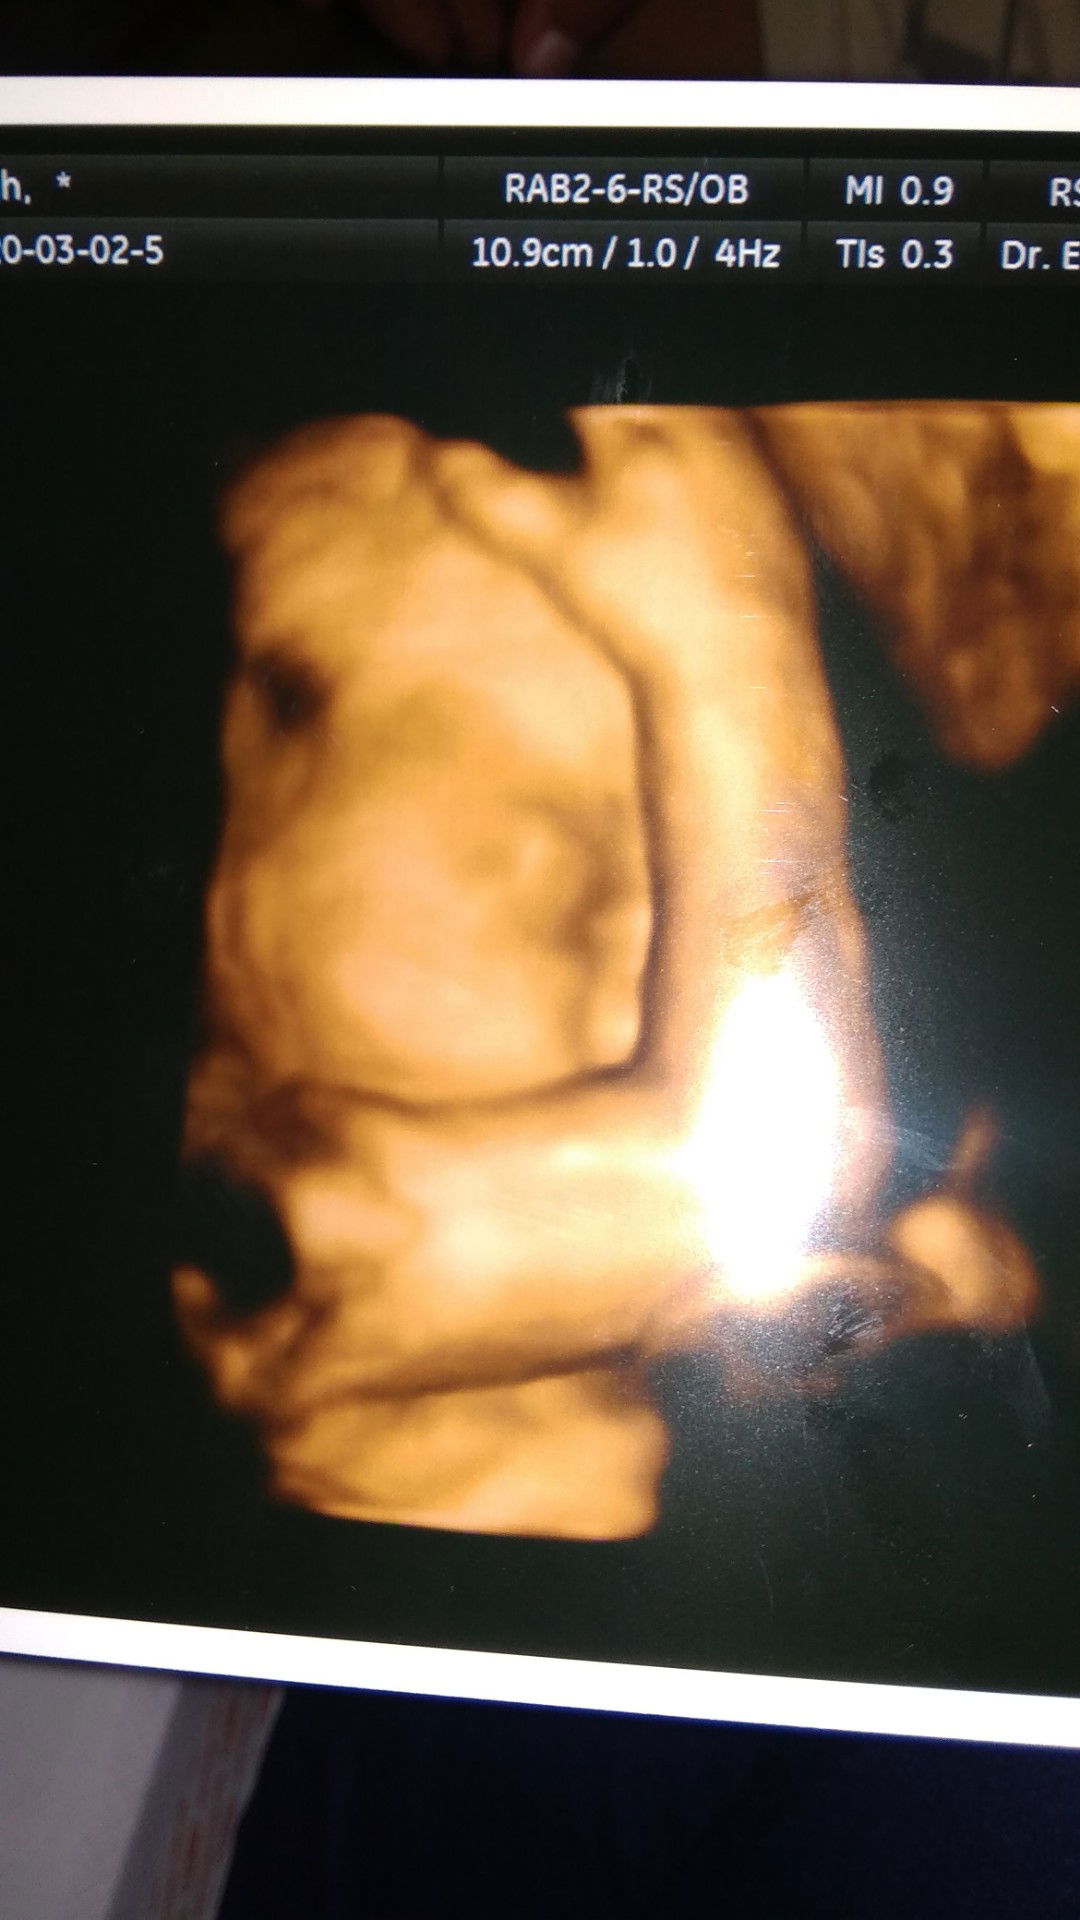

31week

Alhadulilah sehat semua

• hasil USG 4D 31week doain y Bun semoga sehat sampe lahiran nanti ga sabar pengen cepet ketemu baby g...